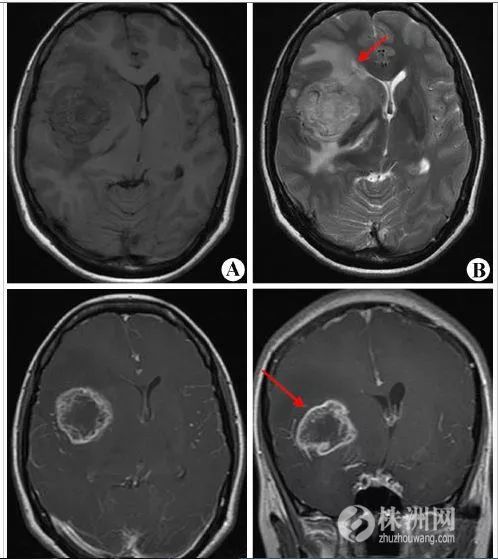

2017年徐州医学院的Yang Ming等采用Meta分析总结了多项研究结果后提出长期使用手机增加胶质瘤发病风险,特别是低分化胶质瘤。

手机和脑瘤的关系

关于手机和脑瘤的关系,由于缺乏长期前瞻性队列研究这样强有力证明因果关系的数据,目前还是定性为“可疑致癌因素”,所以不必过分紧张。然而不少研究也发现了两者之间的相关性,因此也不能掉以轻心,特别是常年大量使用手机的用户以及20岁以下的年轻人及少年儿童。